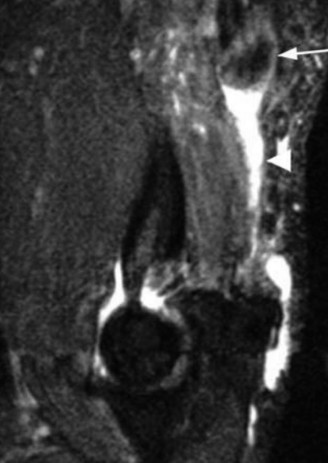

Understand the outcome and prognosis of adhesive capsulitis? CASE 30 Dr. Robert J. Stewart A 44-year-old, right-hand-dominant male with well-controlled diabetes and hypertension presents to clinic with left shoulder pain. The patient denies a history of trauma or injury. He localizes his pain over the superolateral aspect of the shoulder, and it radiates to the deltoid insertion. He has experienced pain over the past few months, but it has progressively become more severe over the past several days. He has difficulty sleeping and with range of motion because of severe pain. While examining the patient, he has a warm and tender left shoulder, and while performing a range of motion evaluation, the patient notes that he has a sensation of “catching.” He has a positive Hawkins sign, negative drop arm test, and pain with a cross body adduction test. A radiograph of the left shoulder is shown in Figure 2–77.

Figure 2–77

What is the most likely diagnosis?

The correct answer is (D). Calcific tendonitis (CT) is a condition characterized by the buildup of calcium hydroxyapatite crystals within tendons. It typically occurs around synovial joints and has been reported in the hip, paraspinal muscles, hand, and foot. It most frequently occurs around the shoulder in patients who are 30 to 50 years old. No one over the age of 71 has been recorded having this condition. Degenerative calcification and reactive calcification have both been proposed as mechanisms for the deposition of calcium. Although the etiology is not understood, most believe that it is a reactive mechanism involving an active, cell-mediated process in a viable tendon. The cell-mediated process has been divided into three distinct phases: precalcific, calcific, and postcalcific. Depending on the stage, imaging, and physical examination characteristics can differ. The calcific stage can be further classified into three phases: formative, resting, and resorption. Rotator cuff arthropathy is seen in older patients with chronic, massive, rotator cuff tears and glenohumeral osteoarthritis. Septic arthritis can look similar to CT, but this patient has had a history of shoulder pain without fever or other risk factors for infection. Answers C and E are incorrect because there are no signs of osteoarthritis of the AC or GH joint on radiograph or physical examination.

Which structure is most likely to be affected on the basis of the information obtained thus far, including the radiograph Figure 2–77?

The correct answer is (C). Calcific tendonitis (CT) is most often localized in the supraspinatus tendon. Radiographic views should include a true AP in internal and external rotation, axillary, and scapular-Y to evaluate for calcium deposits in the tendons of the rotator cuff. There are no reports of the deltoid muscle being involved in CT. Radiographs also help to distinguish resorptive and formative phases. Two radiographic types have been described: Type I (associated with the resorptive phase and acute pain) is a deposit that is fluffy or fleecy in appearance with a poorly defined periphery. Type II (associated with the formative phase and chronic pain) has discrete, homogeneous deposits that have a well-defined periphery.